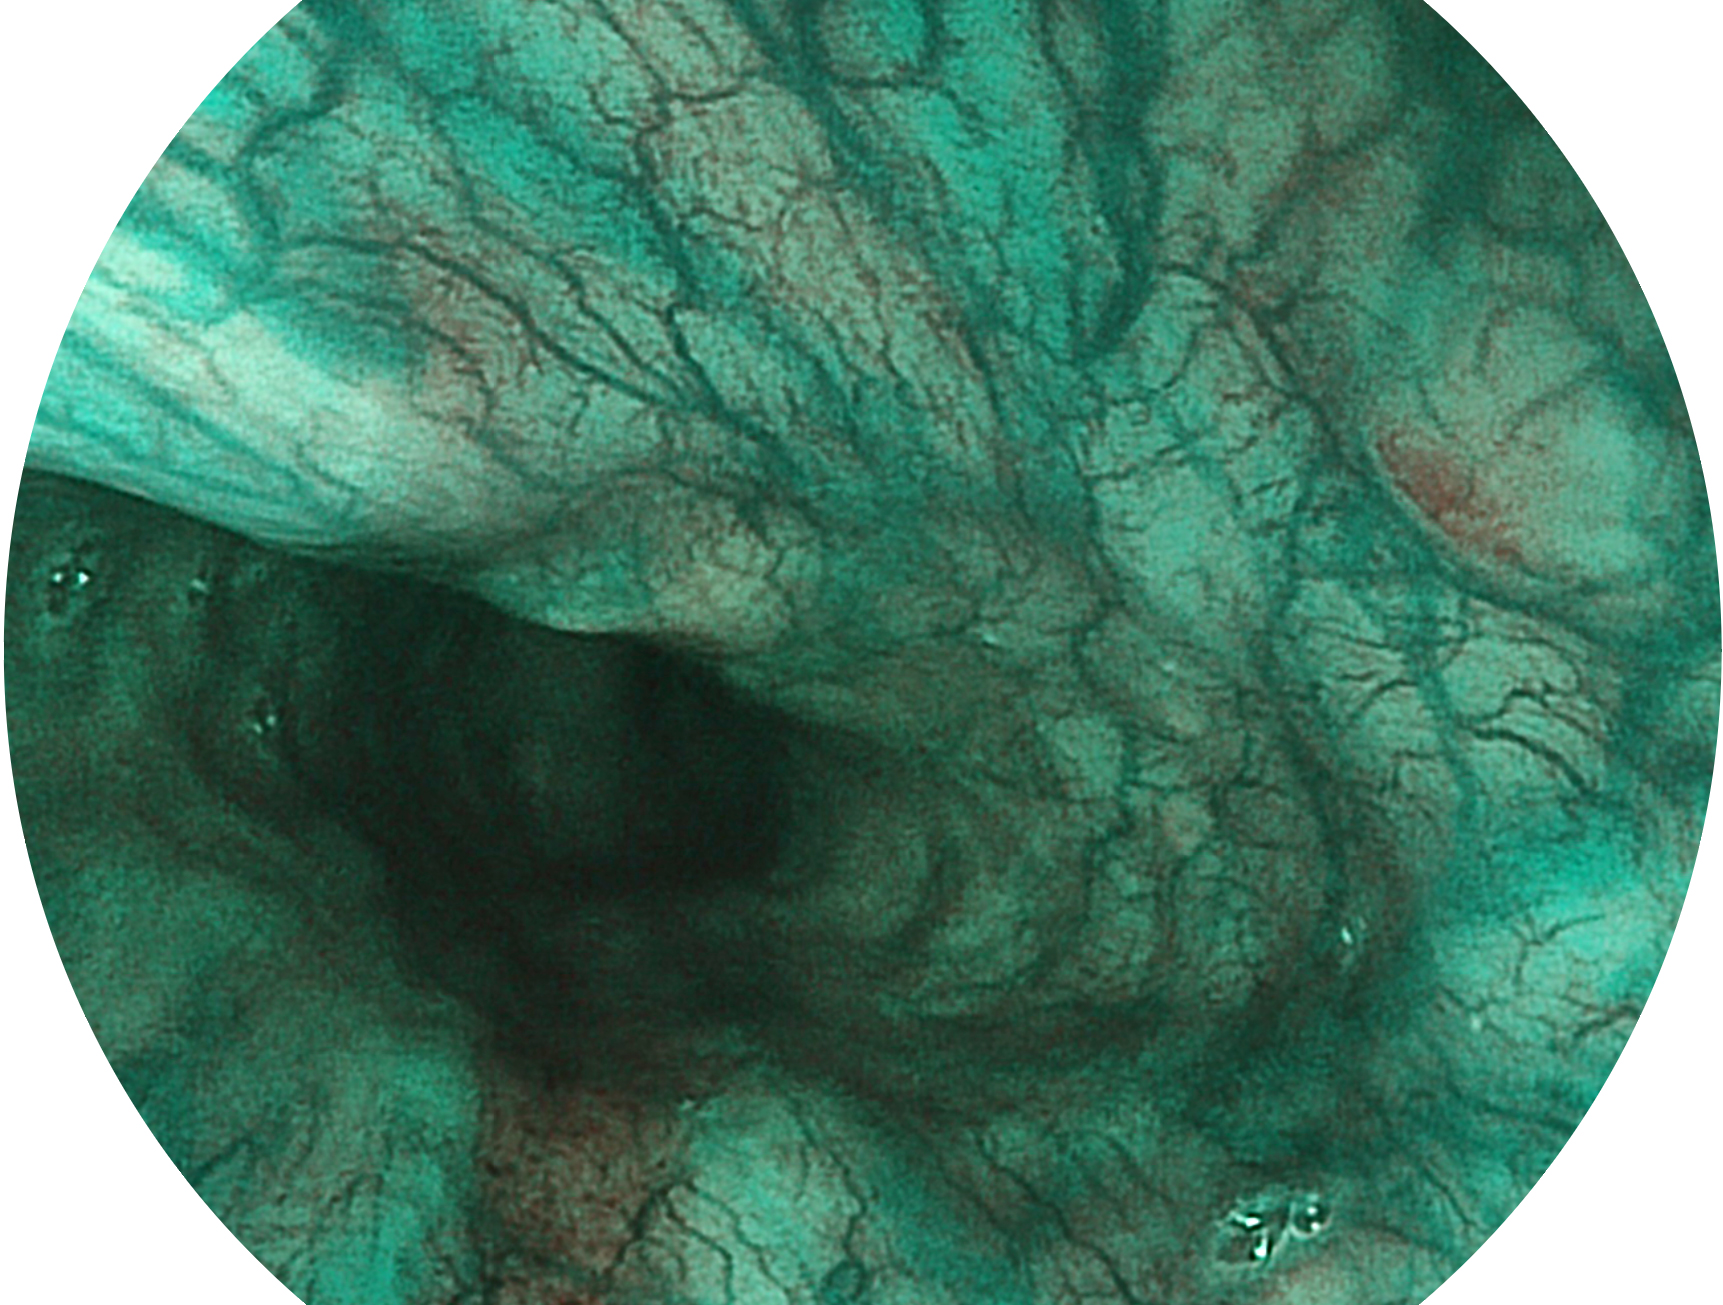

16877太阳集团新开发的内镜染色技术,主要是基于多波长LED 光源的开发,VLS-55Q 四波长LED 光源是由四个不同颜色的LED光按照相应照明模式所规定的特定发光比例进行合束后形成,合束后形成的照明光的光谱由红光、绿光、蓝光及蓝紫光这四个不同的波段范围构成。具有更高光谱自由度,通过光谱比例的控制,实现了聚谱成像技术,英文全称为“Spectral Focused Imaging, SFI”,缩写为“SFI”和光电复合染色成像技术,英文全称为“Versatile Intelligent Staining Technology, VIST”,缩写为“VIST”。